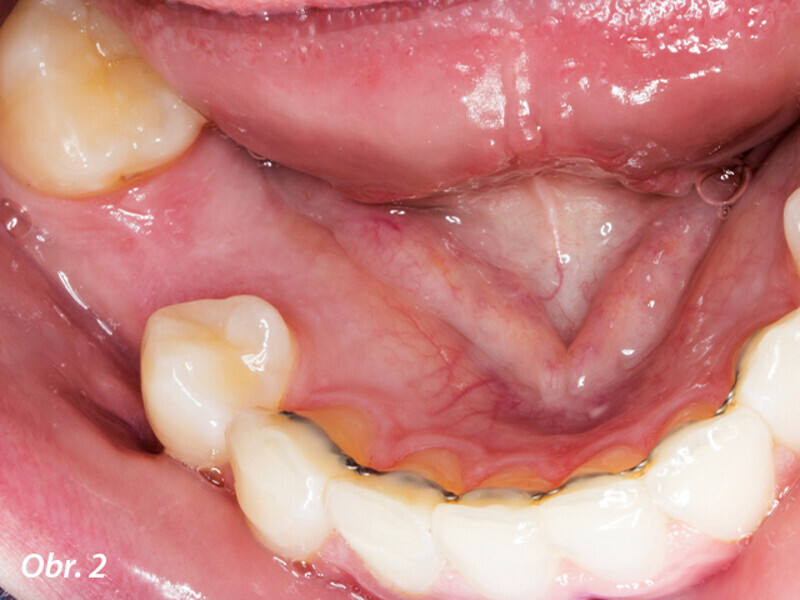

Řízená implantologie za použití řešení Planmeca all-in-one